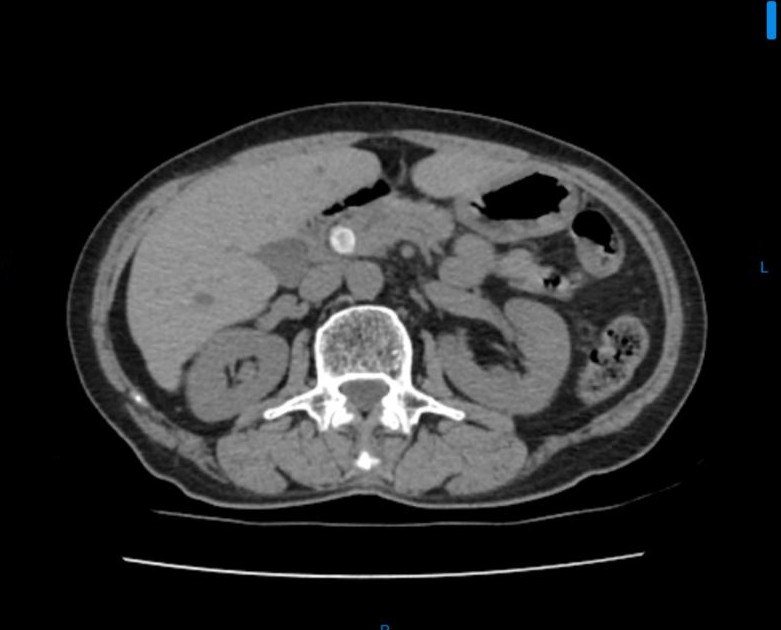

Bn nữ 44 tuổi đau thượng vị nhiều đợt. Đi khám và được chẩn đoán xơ teo thùy gan trái do sỏi gan trái. Sau hội chẩn được chỉ định cắt thùy gan trái nội soi. Trong ca mổ chung tôi đã sử dụng dao hàn mạch Ligasure và Stapler để tiến hành cắt gan trái cho bệnh nhân. Ca mổ đã diễn ra thuận lợi không chảy máu. BN ra viện sau 7 ngày.

Hình ảnh sỏi và phần gan được cắt bỏ qua nội soi.